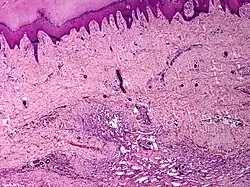

Angiomatosis is a non-neoplastic condition[1] characterised by nests of proliferating capillaries arranged in a lobular pattern, displacing adjacent muscle and fat.[2] It consists of many angiomas.[3]

It is a vascular malformation wherein blood vessels proliferate along with accompanying mature fat and fibrous tissue, lymphatics and sometimes nerves.[2] They may involve skin, subcutaneous tissue, skeletal muscle and occasionally bone.[2]